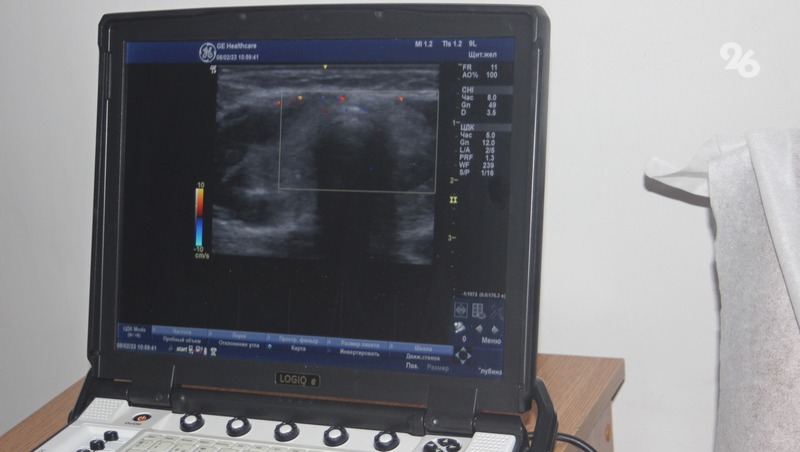

В диагностическом центре Невинномысска в эти дни работают более 20 врачей различных онкоспециальностей, они проводят медицинские осмотры работников промышленных предприятий города.

Готовиться к масштабному медицинскому проекту, проходящему сегодня в крае, начали ещё в 2022 году. Незадолго до приезда «Онкопатруля» на градообразующих предприятиях Невинномысска провели анкетирование, которое прошли порядка 4 тыс. человек. Кроме того, ещё до начала проекта у желающих принять участие в программе взяли первичные анализы, женщинам провели маммографию. В результате 300 человек пригласили на дальнейший полный медосмотр.

В рамках «Онкопатруля» в Невинномысске не только проводится медосмотр, но и мастер-классы, круглые столы для медицинского персонала первичного звена. На мастер-классах для врачей различных направлений рассматривают реальные случаи на примере пациентов, прошедших первичную диагностику при подготовке к мероприятиям.